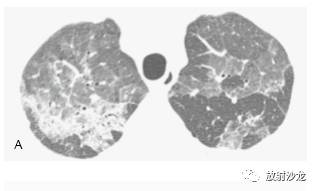

当考虑磨玻璃影的鉴别诊断时,重要的是要知道病例的症状是急性、亚急性还是慢性的(表 5-1)。在这些磨玻璃影原因中,呈典型急性表现 的是肺水肿;肺出血(图5-2);各种肺炎,尤其是诸如耶氏孢子菌肺炎(PJP)(图 5-3, 图 5-7,图5-10)的非典型肺炎, 病毒性肺炎(如巨细胞病毒性),支原体肺炎;急性间质性肺炎(AIP)及其他原 因的弥漫性肺泡损伤(DAD)(图 5-6)和急性 呼吸窘迫综合征(ARDS),包括慢性间质性 肺炎的急性恶化;急性嗜酸性肺炎;急性过敏性肺炎,吸入性和早期放射性肺炎。

亚急性或慢性症状病例中磨玻璃影最常见的病因包括(表 5-1):间质性肺炎,如非特异性间 质性肺炎(NSIP)(图 5-8,图5-11),特发性 或其他特异性疾病,如硬皮病或其他胶原血管病,脱屑性间质性肺炎(DIP)(图 5-12) ,呼吸细支气管炎-间质性肺疾病(RB-ILD),过敏性肺炎(HP)(图 5-5,5-13), 机化性肺炎(OP),药物反应,慢 性嗜酸性肺炎(图 5-14),淋巴样间质性 肺炎(LIP),Churg-Strauss综合征, 类脂质肺炎(图5-15)和慢性或反复性吸入性肺炎,非黏液性和黏液性肺腺癌(图5-16) , 结节病,和肺泡蛋白沉着症(PAP)(图 5-17)。